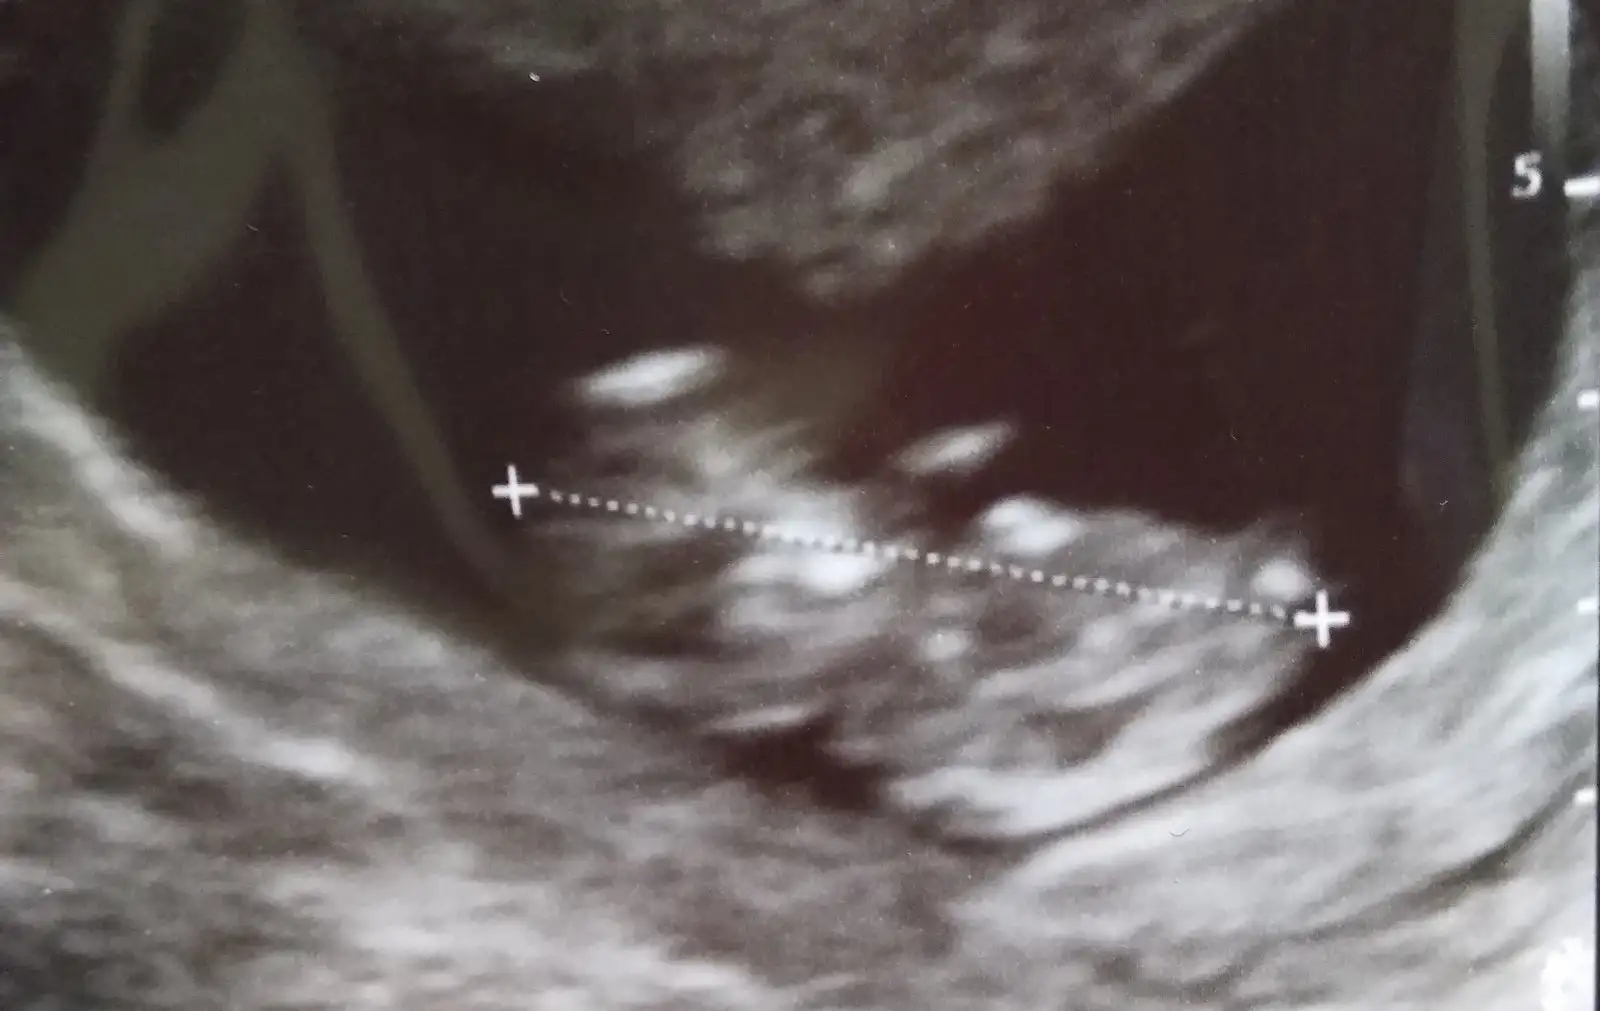

Bana da minik bi prens gibi geldi :)Kızlar ağrılarımdan dolayı dayanamadim geldim doktora bebek iyi neyse ki. Nubcular ben çok anlamıyorum ama ikinci erkekim geliyor sanki 11+2